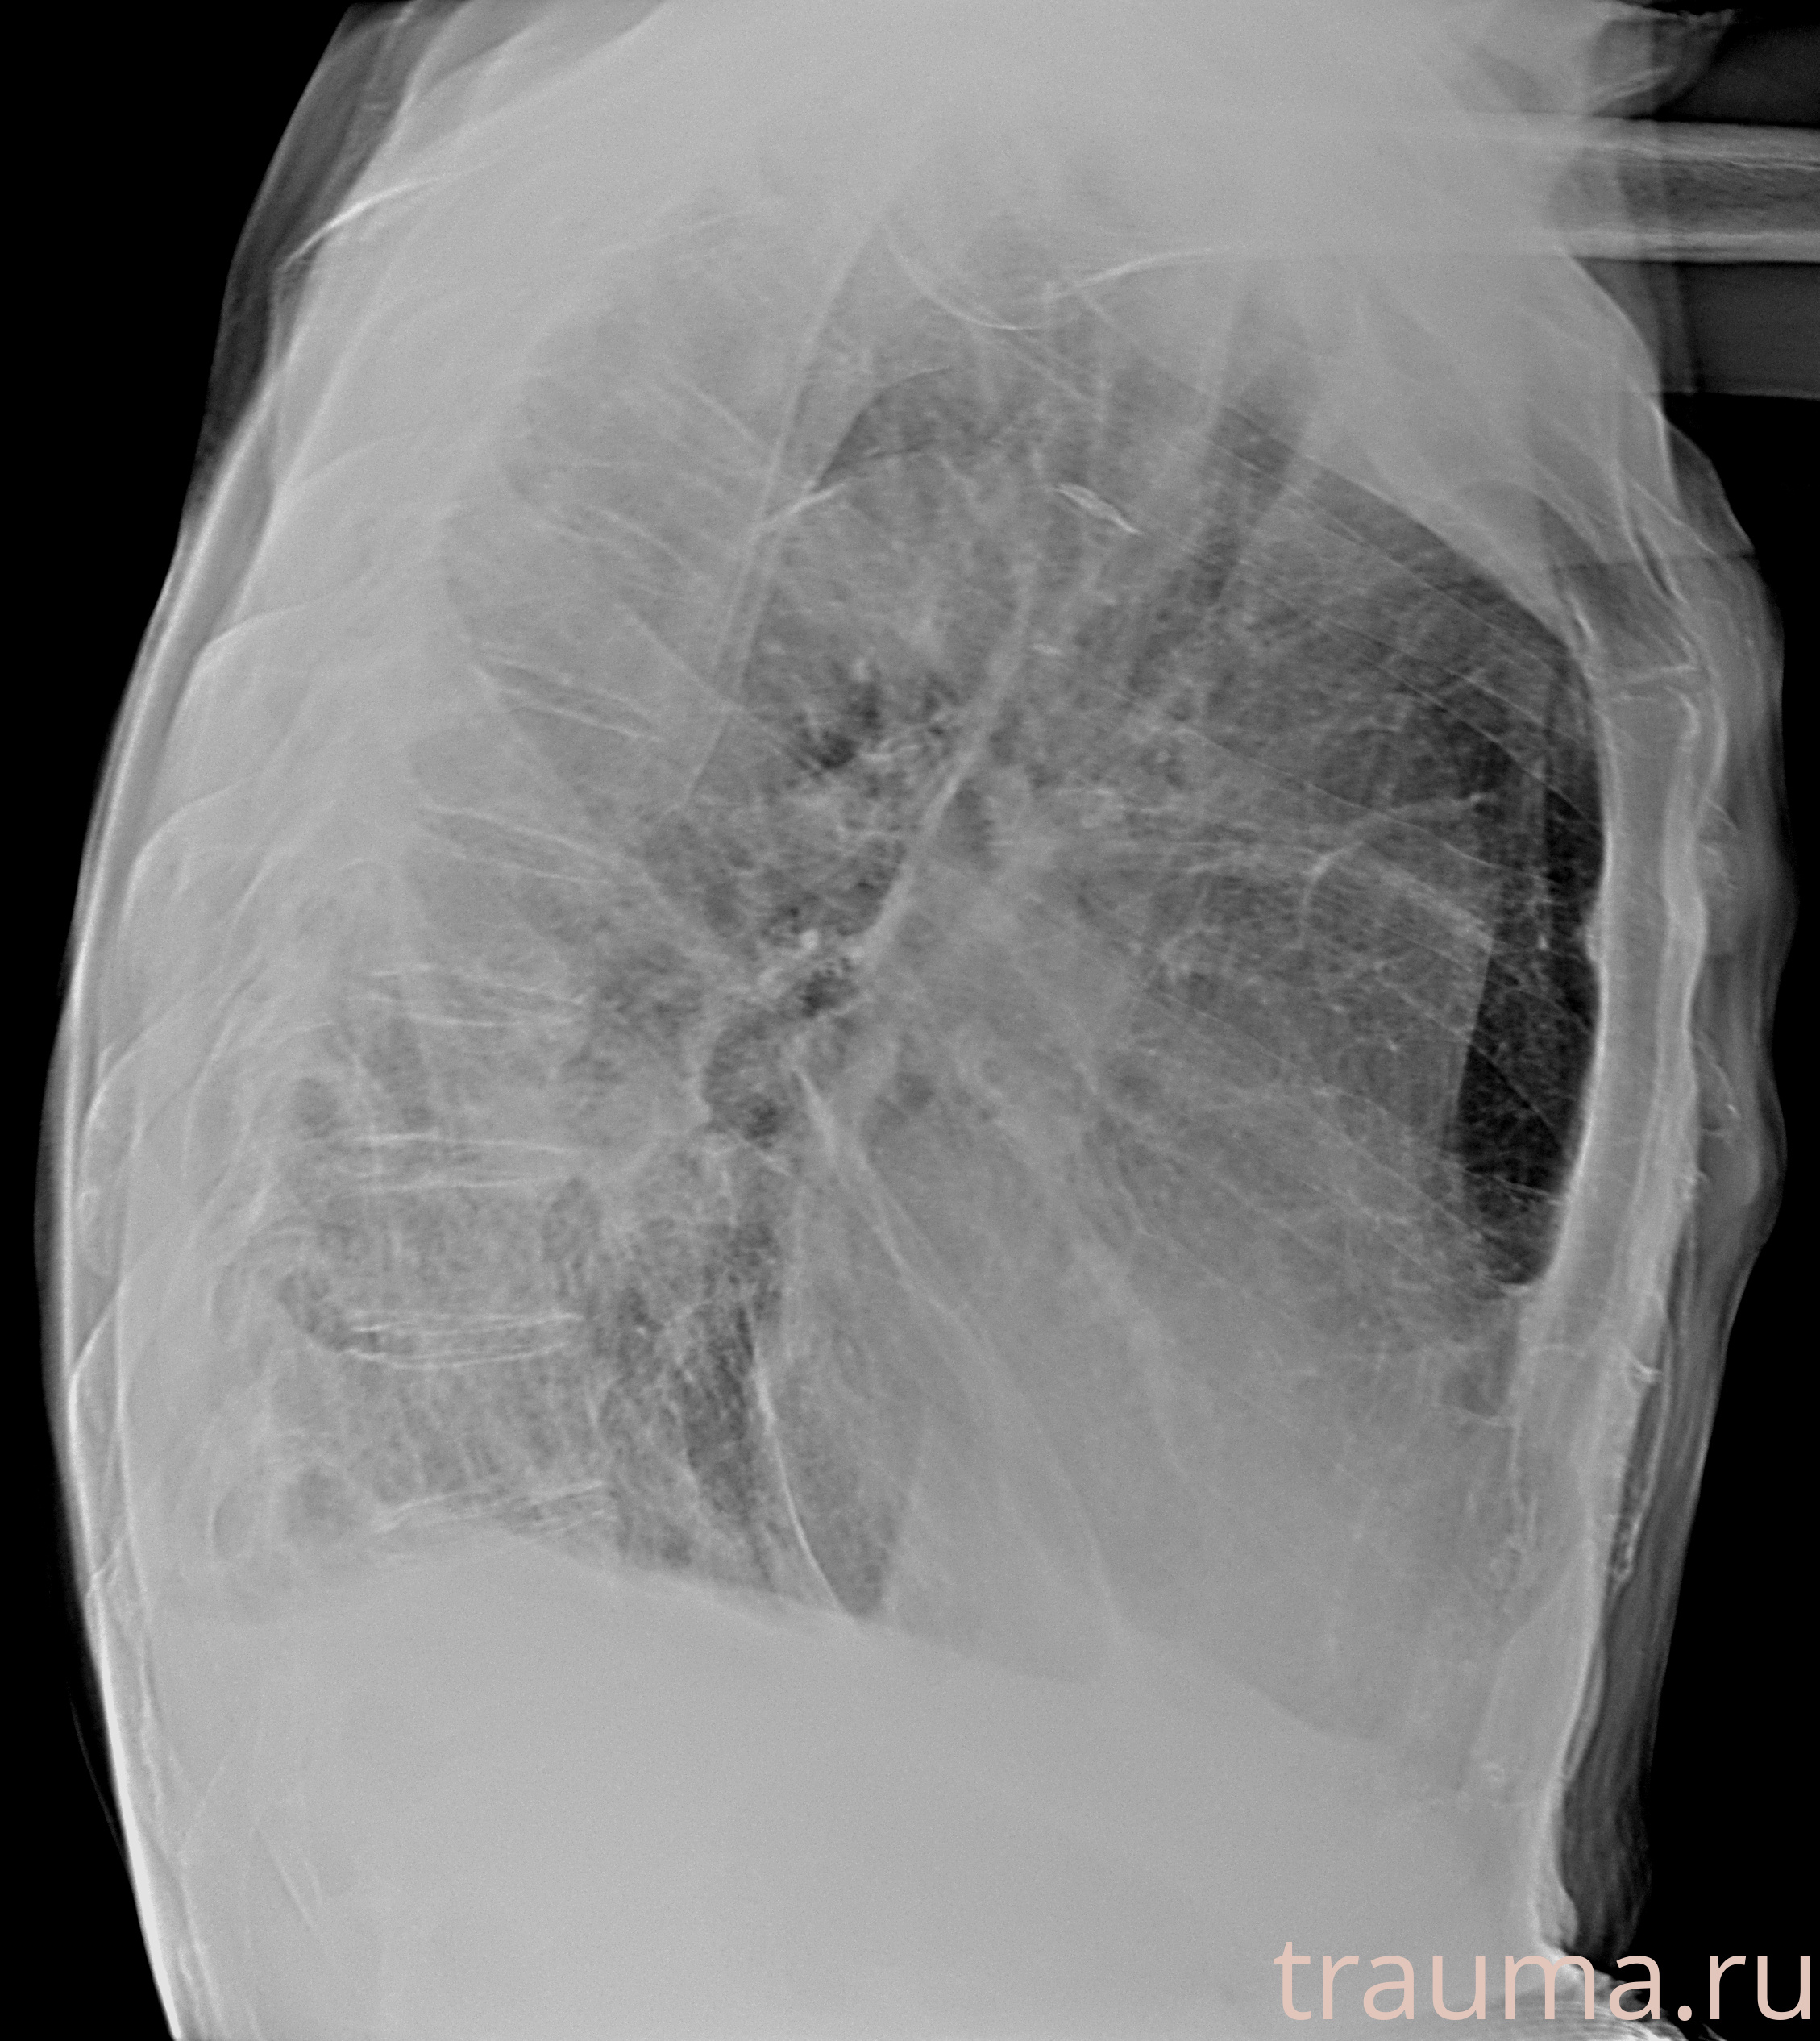

Рентген на дому: по вашему адресу приезжает врач-рентгенолог, травматолог-ортопед с мобильным рентгеновским аппаратом, проводит диагностику травмы или заболевания, делает необходимые рентгенограммы, дает рекомендации по дальнейшему лечению. Получить качественные снимки в домашних условиях возможно благодаря уникальной методике, разработанной МосРентген Центром для института  Склифосовского